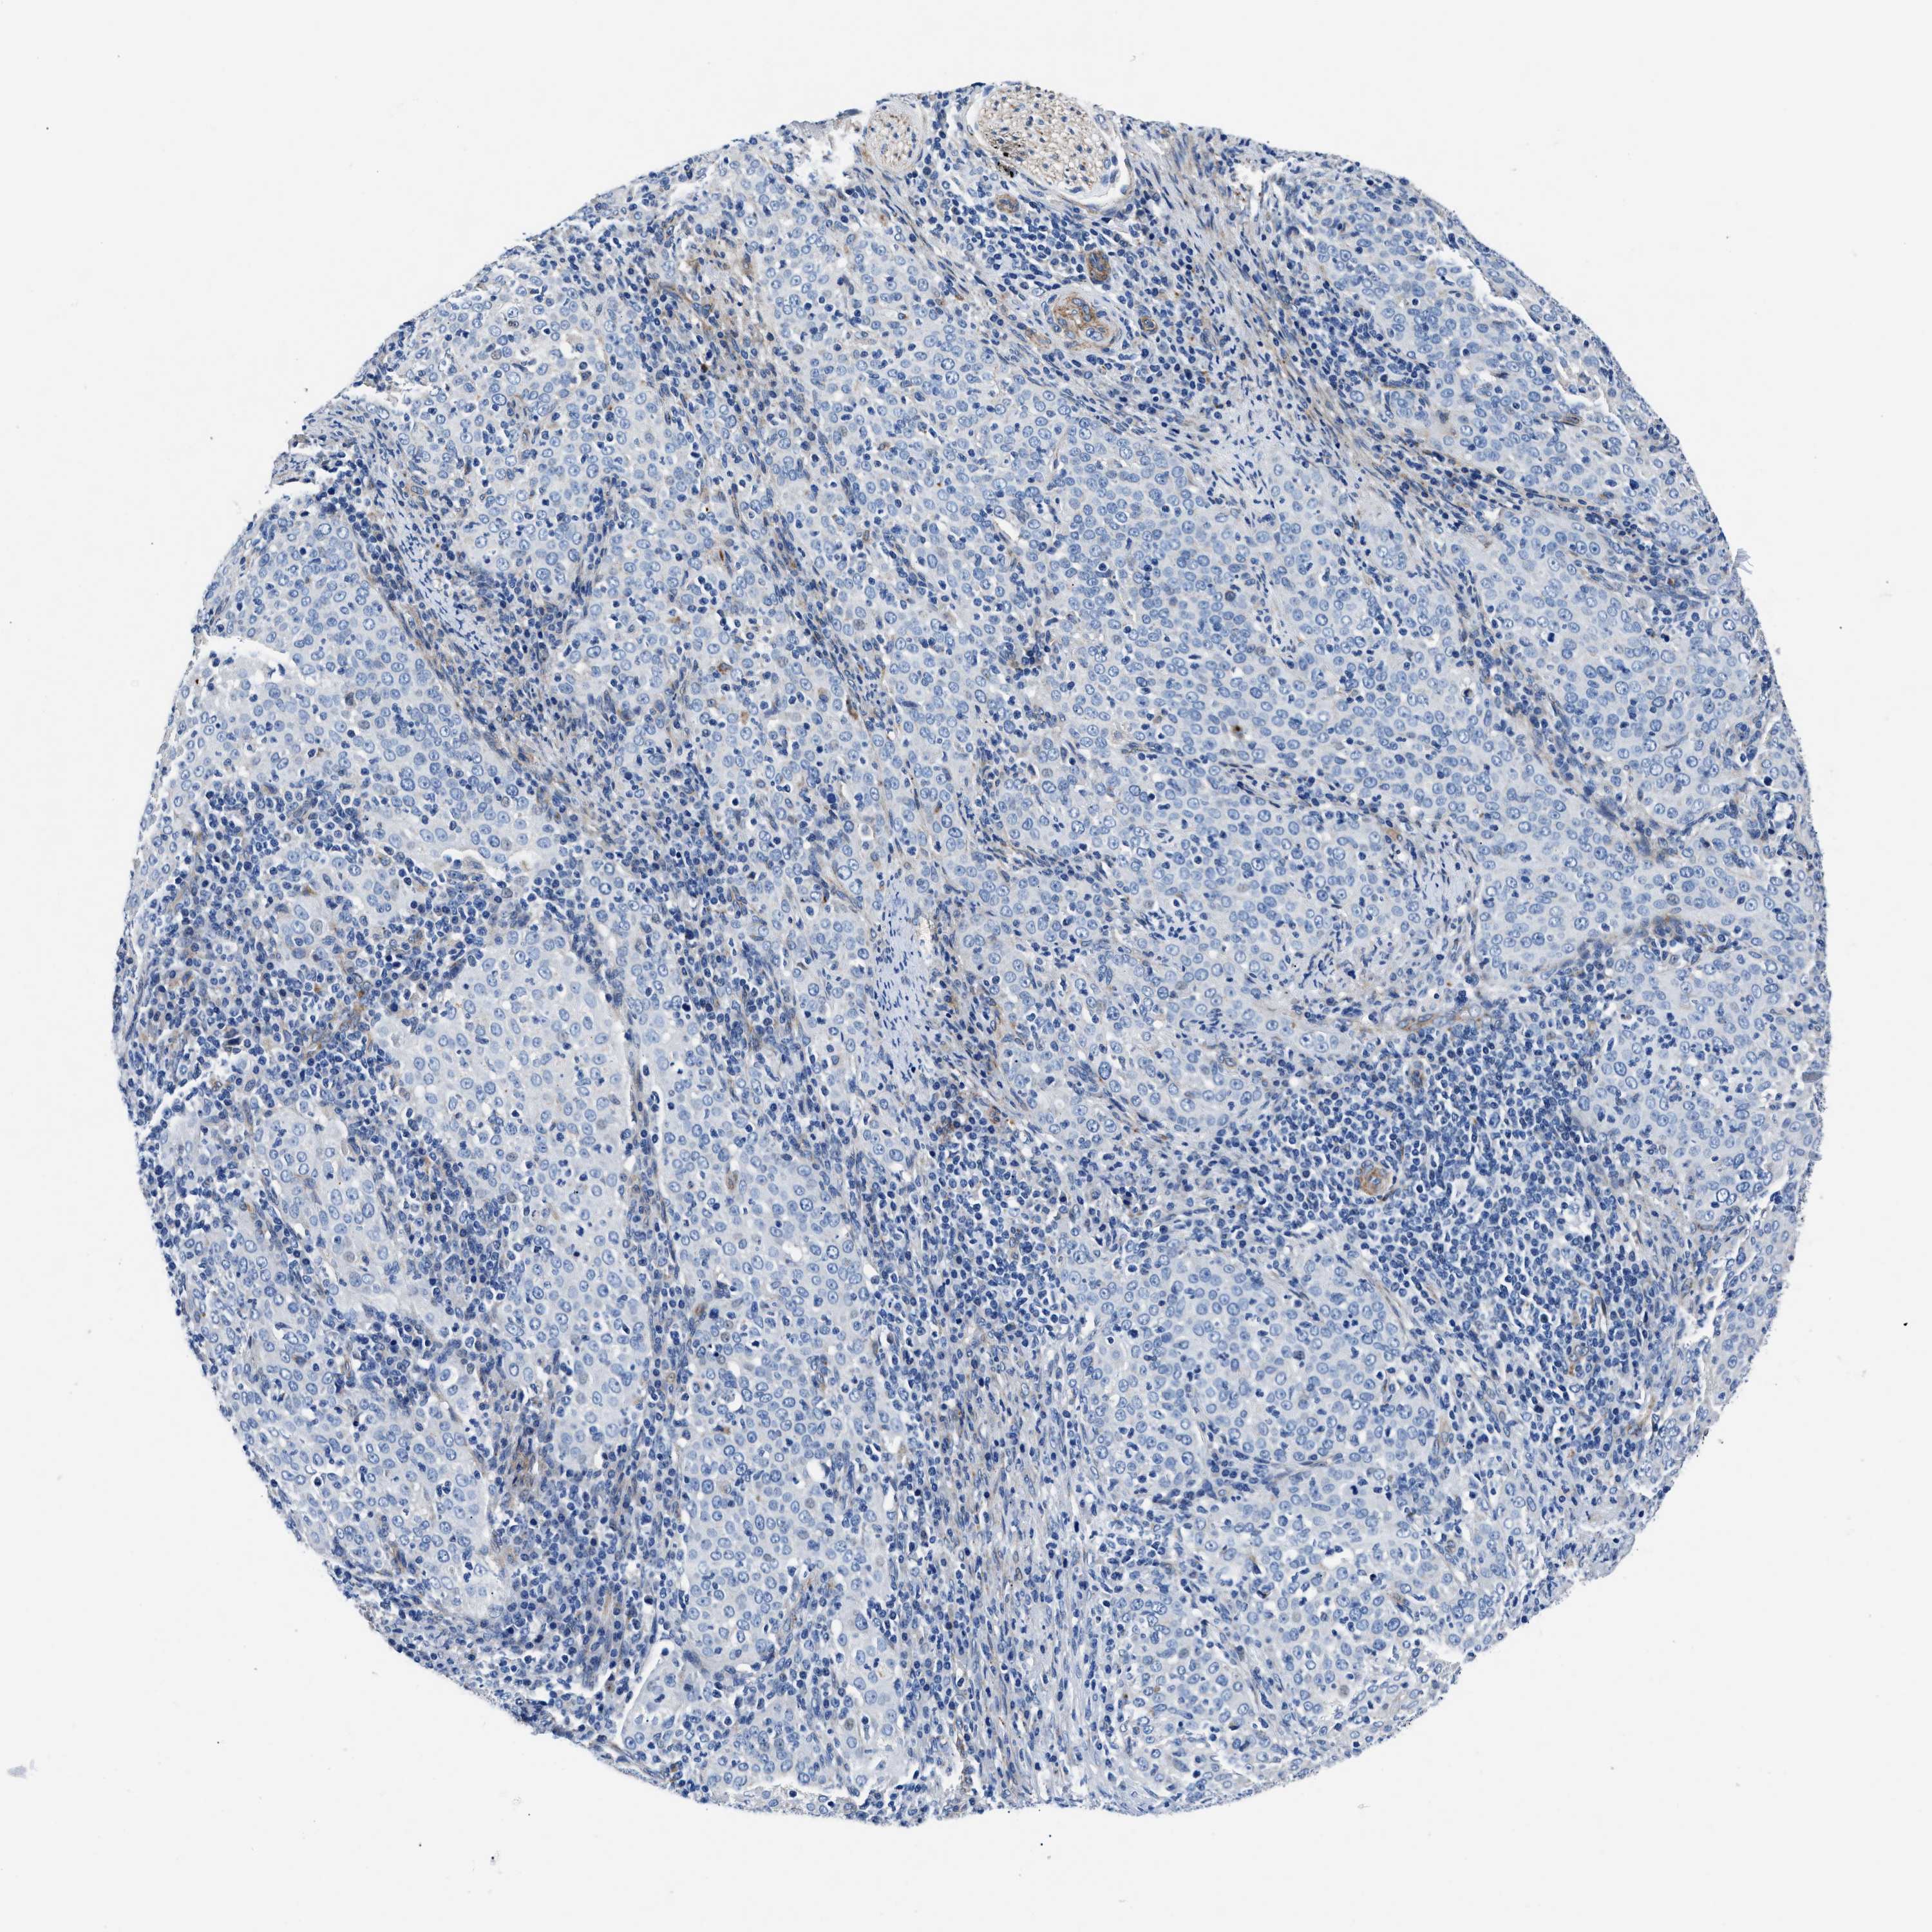

CERVICAL CANCER - Protein expressioni

A mouse-over function shows sample information and annotation data. Click on an image to view it in a full screen mode. Samples can be filtered based on level of antibody staining by selecting one or several of the following categories: high, medium, low and not detected. The assay and annotation is described here.

Note that samples used for immunohistochemistry by the Human Protein Atlas do not correspond to samples in the TCGA dataset.

Antibody stainingi

Antibody staining in the annotated cell types in the current human tissue is reported as not detected, low, medium, or high, based on conventional immunohistochemistry profiling in selected tissues. This score is based on the combination of the staining intensity and fraction of stained cells.

Each image is clickable and will lead to virtual microscopy that enables deeper exploration of all samples and also displays staining intensity scores, fraction scores and subcellular localization as well as patient and tissue information for each sample.

Antibody CAB001960

Antibody CAB016353

Staining

High

Medium

Low

Not detected

Intensity

Strong

Moderate

Weak

Negative

Quantity

>75%

75%-25%

<25%

None

Location

Nuclear

Cytoplasmic/membranous

Cytoplasmic/membranous,nuclear

Adenocarcinoma, NOS

Squamous cell carcinoma, NOS